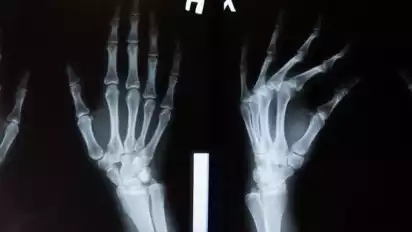

Ilustrasi pemeriksaan kondisi tulang.